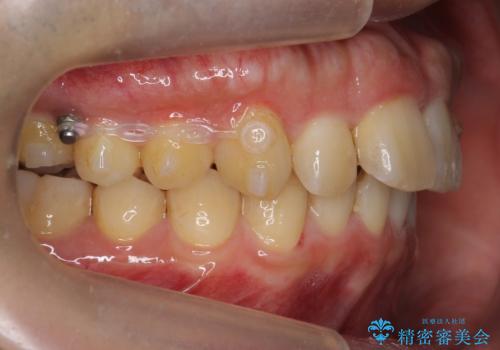

歯を抜かずに奥歯を後ろに動かすために、矯正用のミニスクリューを使用しています。

また、過蓋咬合(深いかみ合わせ)で食いしばりがきつく、歯の移動には大変時間がかかりました。

食いしばりがきついかたについては、長時間マウスピースをはめると奥歯が咬まずに前歯に負担がかかる場合があります。今回は使用時間を短くしたり、下の歯並びを早めにプレートタイプリテーナーに置き換えるような工夫を行い、治療を行いました。